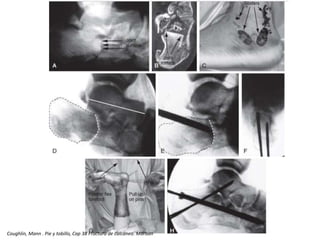

Reducción

Mac Rae , Fractura de calcáneo. cap. 39

Método

Eastwood

• Separa el frag

supero lateral

• Desimpacta

pared medial

• Reduce la

tuberosidad.

Bernirschke

Fernandez

Zwipp

Coughlin, Mann . Pie y tobillo, Cap 38 Fractura de calcáneo. Marban

Coughlin, Mann . Pie y tobillo, Cap 38 Fracturas de calcaneo. Marban

Mac Rae ,Fractura de calcáneo. cap. 39

• 44.

Método Eastwood • Separa elfrag supero lateral • Desimpacta pared medial • Reduce la tuberosidad.

• 45.

• 47.

Coughlin, Mann .Pie y tobillo, Cap 38 Fractura de calcáneo. Marban

• 48.

Coughlin, Mann .Pie y tobillo, Cap 38 Fracturas de calcaneo. Marban